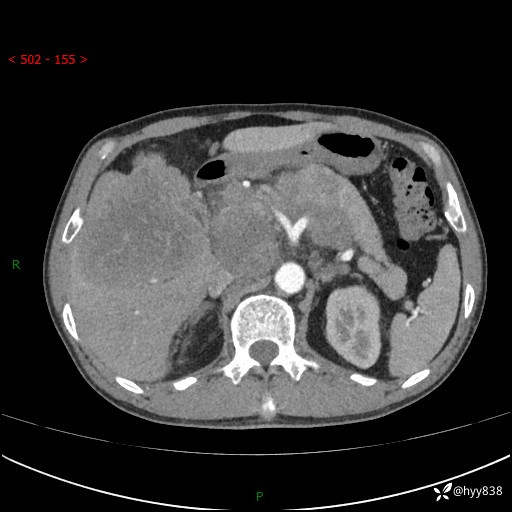

上腹部CT平扫+增强(两期)